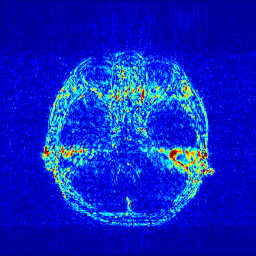

In the CS-MRI inversions, the zero-filled MR images usually serve as the starting point in the iterative optimization. Although the iterative de-aliasing can effectively remove the artifacts and achieve much more pleasing visual quality compared with zero-filled reconstruction, the distortion and information loss is inevitable in the reconstruction. To further illustrate this phenomenon, we compare the pixel-wise reconstruction errors among the zero-filling reconstruction and other reconstruction models of the MR image in Figure 2.

We take the difference between the absolute reconstruction error of zero-filled and the compared CS-MRI methods and only keep the nonnegative values, which can be formulated as

md=(|xfsx¯p||xfs𝒵(y)|)+.subscript𝑚𝑑subscriptsubscript𝑥𝑓𝑠subscript¯𝑥𝑝subscript𝑥𝑓𝑠𝒵𝑦m_{d}={\left({\left|{{x_{fs}}-{\overline{x}_{p}}}\right|-\left|{{x_{fs}}-{\cal Z}(y)}\right|}\right)_{+}}. (8)

Where the operator ()+subscript{\left(\cdot\right)_{+}} set the negative values to zero. We only keep the nonnegative values in the map, which results the filtered difference map. We show the corresponding filtered difference map mdsubscript𝑚𝑑m_{d} in figure 3 in the range [0 0.2]. The bright region means the better accuracy of zero-filled reconstruction. We observe the zero-filling reconstruction provide better reconstruction accuracy on some regions, indicating the information loss in the reconstruction occurs.

Figure 3: The filtered difference map d𝑑d between the reconstruction errors of the zero-filled reconstruction and recent CS-MRI inversions.